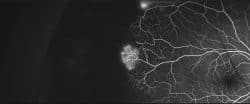

Sickle cell retinopathy

Sickle cell disease is an imported recessive autosomic genetic disease. Around 40% of the patients develop, among others, alteration of peripheral vessels of the retina, according to traditional studies. 14 patients, with an average age of 21, are studied with wide-field angiography (WF-AGF). Though peripheral ischemia is present in all patients, shunts (62.5%) and neovessels…